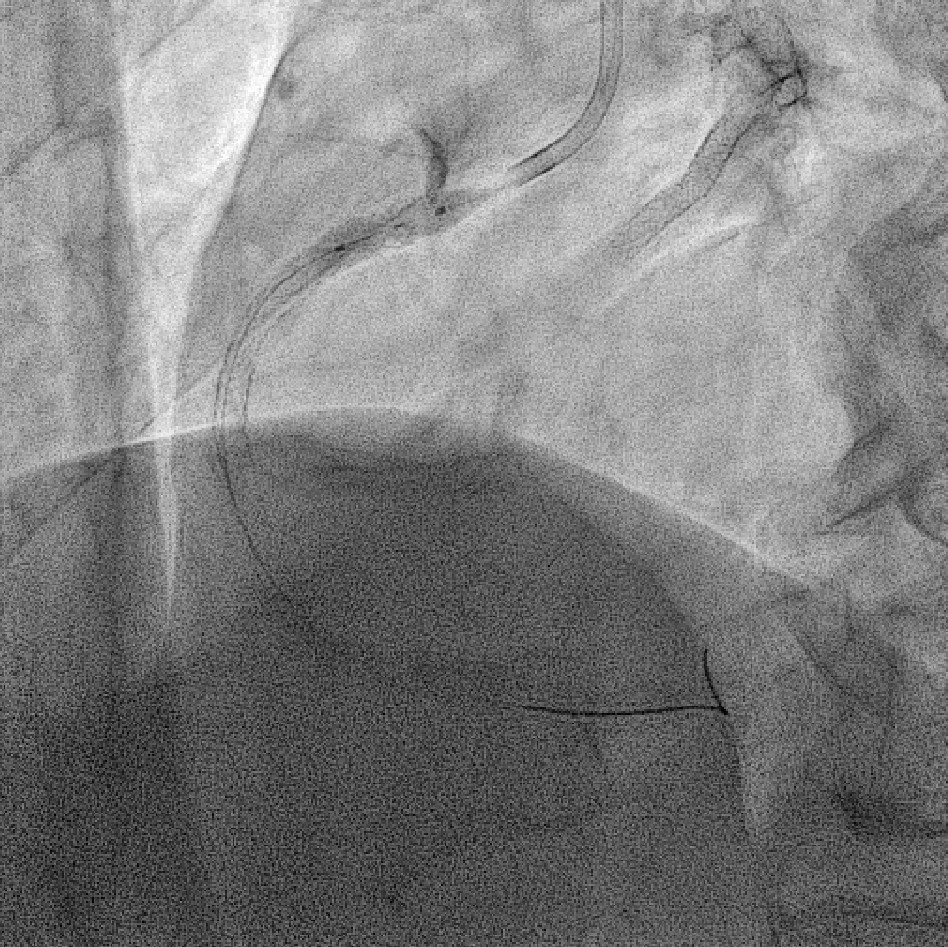

Coronary angiography revealed 81% in-stent restenosis at the right coronary artery ostium, worsened since February 2025. Proximal and mid RCA stents were patent; distal RCA was patent but smaller in caliber . Left main and LAD stents showed no progression, though 30–60% restenosis was seen in proximal to mid LAD. Left circumflex artery was nearly totally occluded from ostium to proximal segment, with preserved flow in mid and distal segments, similar to prior study.

We advanced a 6F JR 4.0 SH 100cm guiding catheter and crossed the RCA ostial lesion using a Fielder FC guidewire. Pre-dilatation was performed with Ryurei 1.5¡¿15mm balloon. IVUS was then performed, revealing a patent stent in the proximal to mid RCA. However, the ostial RCA stent was under-expanded, with smooth muscle compressing the stent from outside. Balloon pre-dilatation was carried out using an NC Euphora 4.0¡¿12mm balloon, inflated up to 22 bar. However, the lesion was resistant and could not be fully dilated. We then applied a 4.0mm intravascular lithotripsy balloon with a total of 100 shocks delivered. But the effect was still minimal. The IVUS showed limited additional plaque fracture or vessel expansion. We tried NC Sapphire II 4.5¡¿8 mm balloon inflation to 18 bar, but it was ineffective due to balloon slippage. The angiogram after oversized NC dilation showed residual stenosis of 59%. We then selected a Wolverine Cutting Balloon 4.0¡¿10 mm and initiated dilation to 6 bar, which resulted in easy slippage again. Subsequent oversized dilations were performed at 18 bar, after which the lesion was successfully dilated. Using a Runthrough Floppy guidewire with the floating wire technique, a drug-eluting stent Biofreedom Ultra 4.0¡¿14 mm was deployed in the ostial RCA ISR. We inflated at 14 bar for 14 seconds, repeated twice. Final post-dilatation was performed with an Accuforce 4.0¡¿15mm balloon. The final IVUS showed good stent placement and expansion. We closed the procedure.